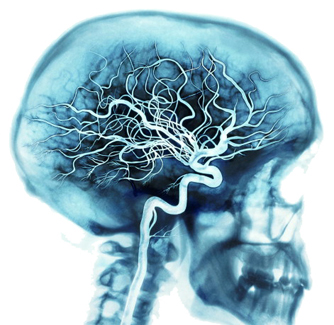

2. Versorgungsleitungen

Eines der wichtigsten Gefäßnetze Ihres Körpers ist für die Versorgung des Gehirns zuständig.

Mit jedem Herzschlag transportieren die Arterien rund 20 bis 25 Prozent Ihres Blutes in Ihr Gehirn, wo Milliarden Zellen etwa 20 Prozent des Sauerstoffs und der Nährstoffe nutzen, die in Ihrem Blut enthalten sind.

Wenn Sie angestrengt nachdenken, kann Ihr Gehirn bis zu 50 Prozent des Sauerstoffs und der Nährstoffe aufbrauchen.

Das gesamte Gefäßnetz beinhaltet neben Arterien auch Venen und Kapillare.